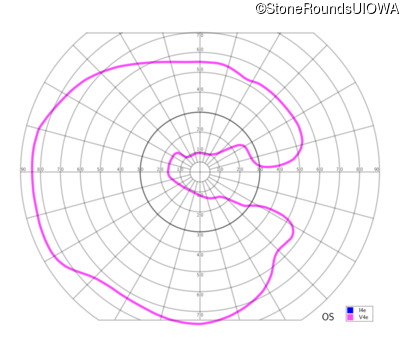

This 81 year old man began using a flashlight to read menus in his 40's. At age 75 his ophthalmologist noticed abnormal fundus findings and referred him to a retina specialist.

| OD | OS | ||